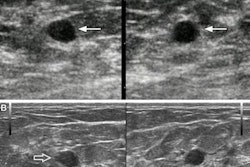

The team tested the technique using mouse models, administering a fluorescently labeled albumin tracer through the nasal canal. Then, the researchers intravenously injected microbubbles and administered focused ultrasound waves aimed deep in the brain at the thalamus. They compared results to control groups, which included tracer administration with focused ultrasound but without microbubbles and tracer administration without either.

This microscopic image reveals the enhanced glymphatic transport of an intranasally delivered tracer (red), achieved using ultrasound combined with microbubbles. Image courtesy of the Chen Lab, Washington University in St. Louis.Through 3D imaging of the treated side of the brain, they found that the combined method improved the transport of the tracer through the blood vessels. They also found evidence of focused ultrasound-enhanced penetration of the tracer from the perivascular space into the interstitial space, primarily along arterioles. The control groups meanwhile showed lower tracer accumulation.

The researchers also used the combined method after injecting the tracer directly to the cerebral spinal fluid. While this method is invasive, the team did so to further validate its results. It found that focused ultrasound with microbubbles improved tracer transport along vessels at the targeted brain site by "about two- to threefold compared with the nontargeted side."

For the arterioles, the researchers found that the average albumin fluorescence intensity in the treated brain region improved by 8.75-fold in the intranasal administration group and 3.49-fold in the ICM group when compared to the nontreated side (p < 0.05 and p < 0.01, respectively). They also noted smaller-scale improvements in the capillaries and venules.